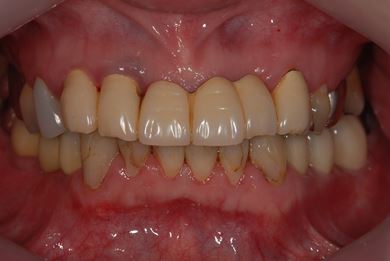

インプラントの症例写真 IMPLANT

骨再生インプラント治療

| カテゴリー | 【インプラント治療】【セラミック治療】 | ||||||||||||||||||||||||||||||||

| 性別/年齢 | 女性 / 40歳 | ||||||||||||||||||||||||||||||||

| 主訴 | 右下のブリッジが外れているかもしれないという診断を受けましたが、開けてみないとわからない、場合によっては部分入れ歯と言われ、セカンドオピニオンを希望。腫れがあるのも気になります。 | ||||||||||||||||||||||||||||||||

| 治療方針 | 右下奥、骨再生法によりインプラント治療を可能にする。 | ||||||||||||||||||||||||||||||||

| 治療内容 | インプラント3本(GBR、テンポラリーインプラント+仮歯)、ハイブリッドセラミックブリッジ3本、ハイブリッドセラミッククラウン2本 | ||||||||||||||||||||||||||||||||

| 総治療費 | 1,524,338円 | ||||||||||||||||||||||||||||||||

| 治療期間 | 1年0ヶ月 |